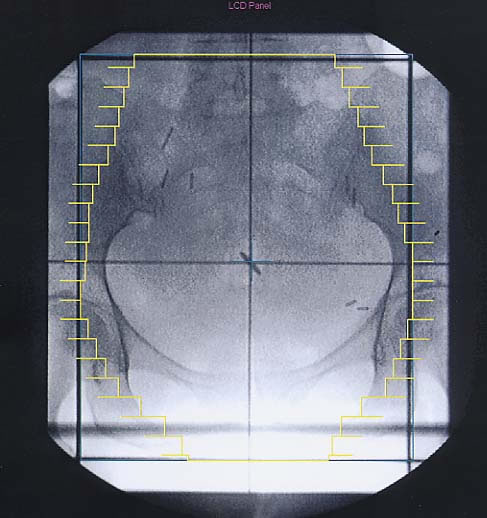

Gynäkologische Tumore des Beckens: Simulationsbild